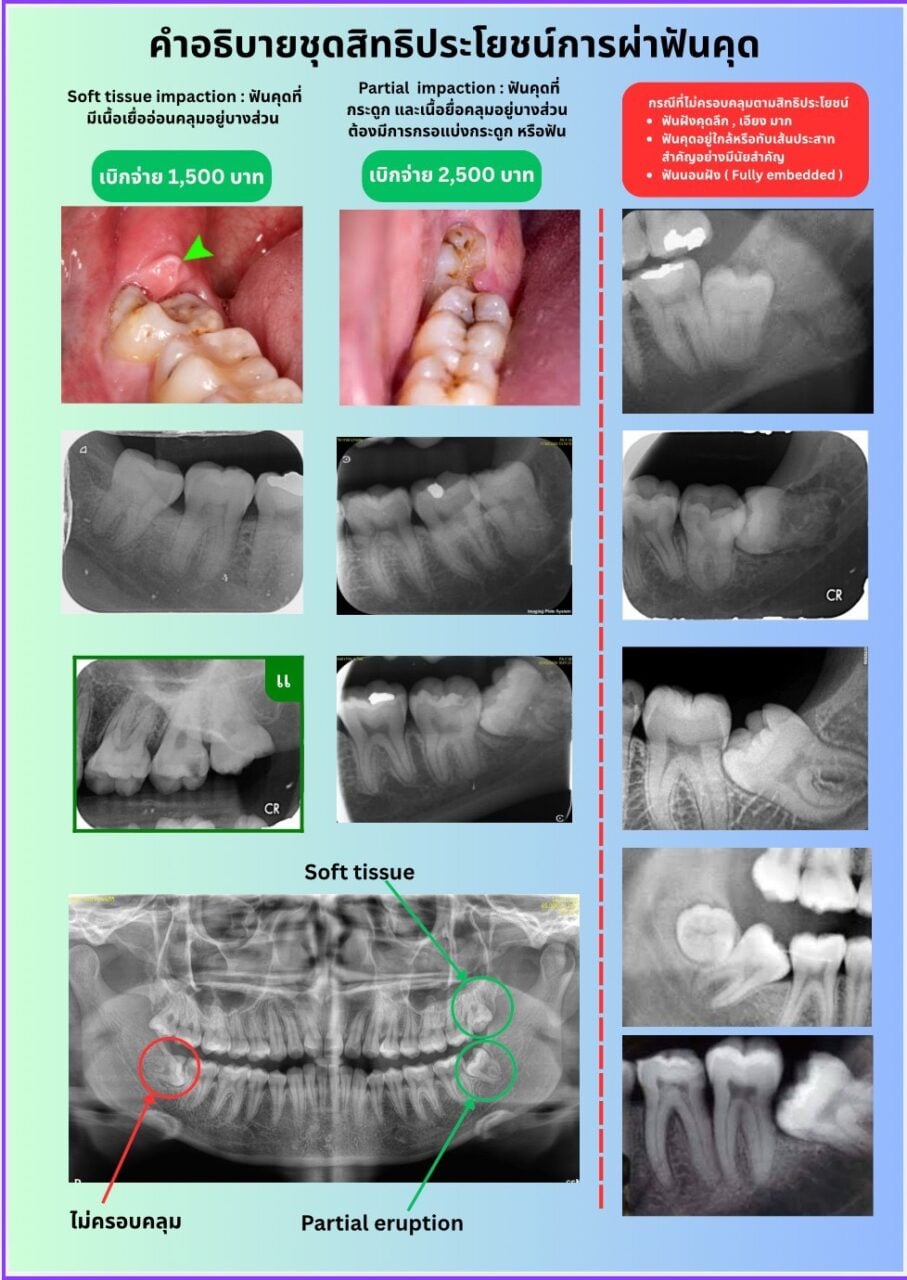

สำหรับสิทธิประโยชน์ผ่าฟันคุดของประกันสังคม จะครอบคลุมเฉพาะ ฟันคุดที่ขึ้นไม่ได้เนื่องจากมีเนื้อเยื่ออ่อนคลุมอยู่บางส่วน (Soft Tissue Impaction Tooth) และฟันคุดที่อยู่ในกระดูกบางส่วนที่ไม่ซับซ้อน (Partial Bony Impaction Tooth) เท่านั้น ส่วนฟันคุดที่อยู่ในกระดูกบางส่วนแบบซับซ้อน ฟันคุดที่มีกระดูกคลุมอยู่ทั้งซี่ (Completed Bony Impaction Tooth) และฟันฝัง (Embeded tooth) จะไม่อยู่ในสิทธิประโยชน์ที่ประกันสังคมกำหนดไว้

สำหรับฟันคุดที่อยู่ในกระดูกบางส่วน (Partial Bony Impaction Tooth) ที่ทันตแพทยสภาเสนอต่อสำนักงานประกันสังคม จะเป็นกรณีเฉพาะที่ไม่ซับซ้อน มีระดับความยากที่เหมาะสมกับการให้บริการของคลินิกทันตกรรมเอกชนโดยทั่วไป ซึ่งทันตแพทยสภาได้เคยให้ข้อเสนอแนะต่อสำนักงานประกันสังคม ว่าควรมีภาพฟันคุดประกาศอย่างเป็นทางการ เพื่ออธิบายว่าลักษณะฟันคุดและภาพถ่ายรังสีฟันคุดแบบใด ที่ครอบคลุมสิทธิประโยชน์ และแบบใดที่อยู่นอกเหนือสิทธิประโยชน์ เพื่อให้เกิดความเข้าใจกันในการสื่อสารระหว่างสถานพยาบาลและผู้ประกันตน